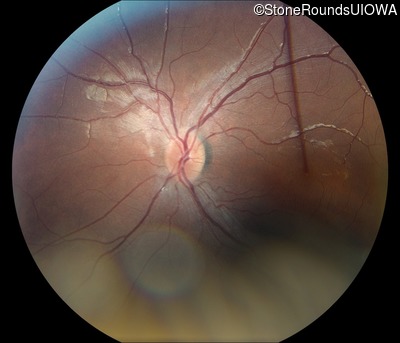

Fundus Photography - Left - 20/50 +2

Exemplar